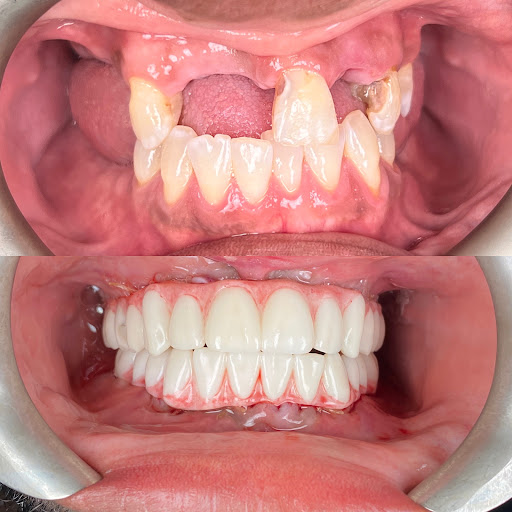

Photos